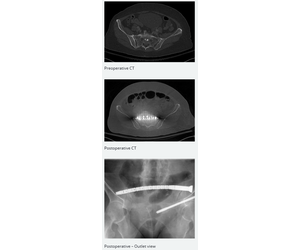

A 68-year-old female with some dysmorphism and mild osteoporosis had a fall in the shower, resulting in a Y-shaped sacral fracture and non-displaced fractures of the superior and inferior pubic ramus.

Fixation in S1 was required because S2 was distal to the transverse component of the sacral fracture.

A standard 7.3-mm screw was inserted at the left hemipelvis.Then. a CurvaFix IM implant (140 mm in length) stabilized the Y-shaped sacral fracture across S1-2.